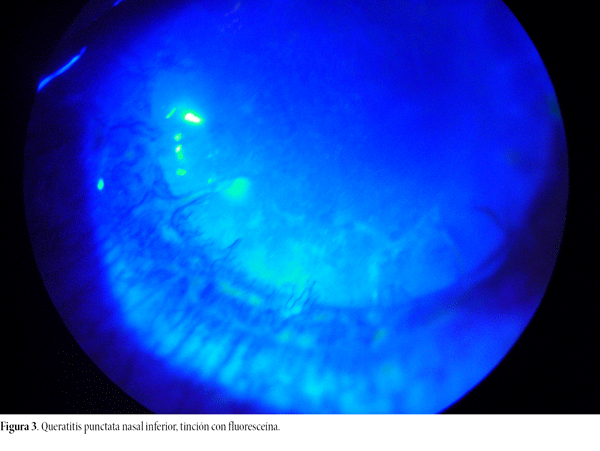

Se recibe para su evaluación, estudio y tratamiento. Vemos dos pequeños infiltrados en puntos ya retirados, múltiples neovasos sobre el injerto, edema corneal más intenso en córnea central e inferonasal, pliegues endoteliales y precipitados queráticos finos (figs. 1 y 2), AV cuenta dedos, inyección conjuntival, células en cámara anterior, queratitis punctata inferior y tinción inespecífica con fluoresceína sobre el injerto (fig. 3). Presión ocular e iris, normales. Se realiza toma de muestra corneal para examen directo, cultivo para bacterias, hongos y amebas. PCR panfúngica, PCR para Acanthamoeba y PCR para virus HSV-1 y HSV-2.

Figura 3. Queratitis punctata nasal inferior, tinción con fluoresceína.